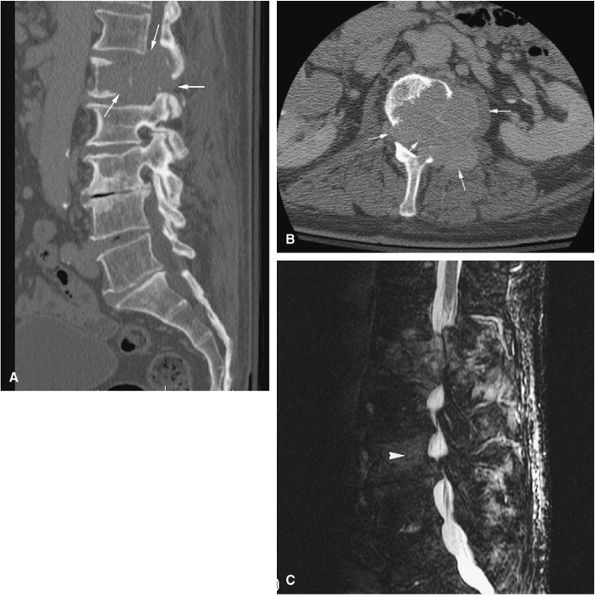

A diffuse inflammatory response involving bone and adjacent soft tissue has been reported in a case of vertebral osteoblastoma.54 CT may be more accurate for the identification of small foci of matrix calcification (Fig. 14-16).

FIGURE 14-15 ● Osteoblastoma arising in the posterior elements of the L2 vertebra is demonstrated on sagittal (A) and axial (B) fat-suppressed T2-weighted fast spin-echo images. Fluid–fluid levels are present (arrows). The tumor is isointense to muscle (arrow) on the axial T1-weighted image (C) and demonstrates enhancement (arrow) following intravenous injection of gadolinium (D). Note the mass effect upon the spinal canal from the tumor.

FIGURE 14-16 ● Internal calcifications (arrow) are identified on an axial CT image in this osteoblastoma arising in the left posterior elements of the L5 vertebra.